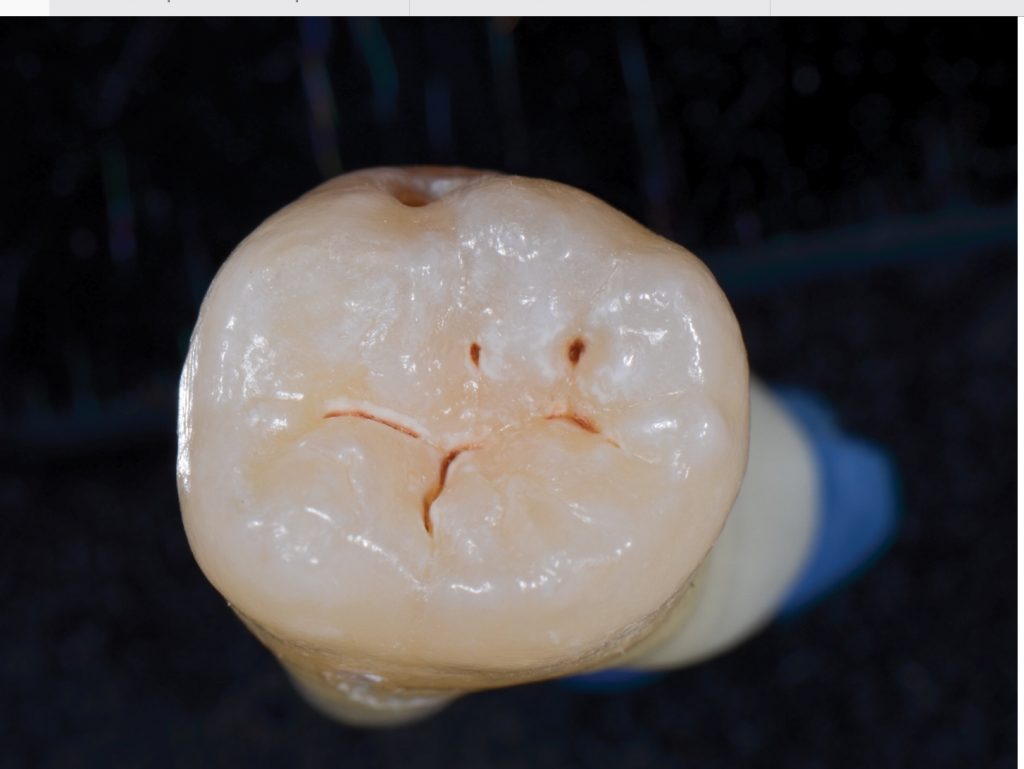

Removing small amount of tooth without needles, drills, or pain

Finished air abrasion filling